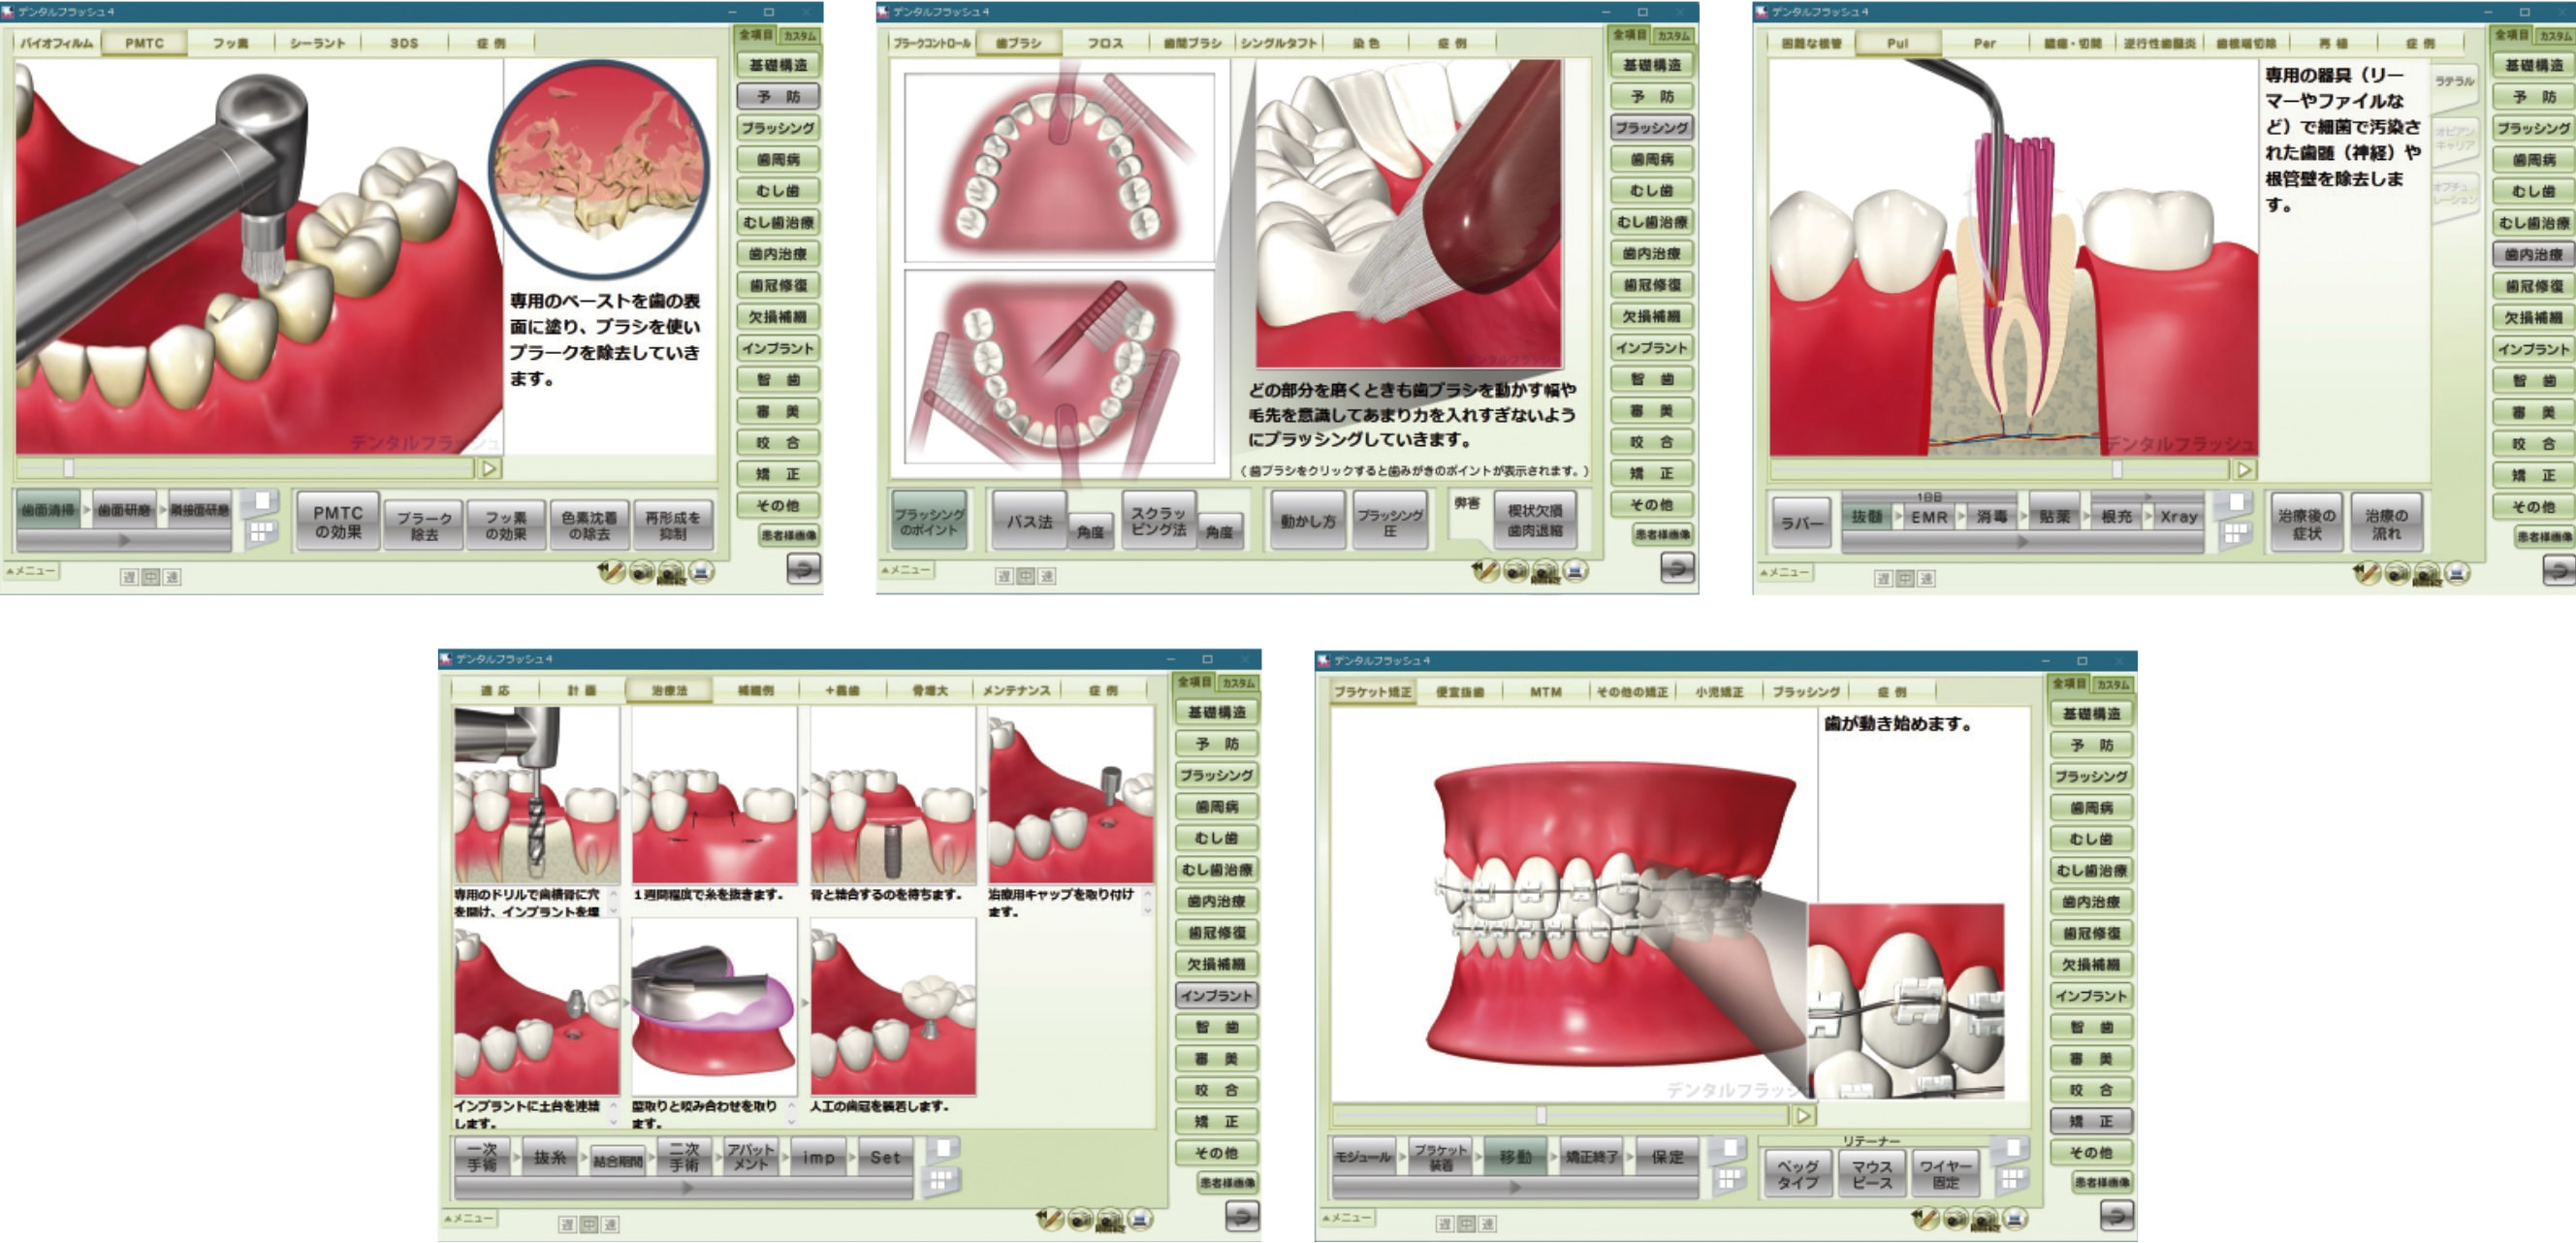

MyGateオプション機能「患者説明ソフトデンタルフラッシュ」

患者さんとの信頼関係を築く、カウンセリング用の3Dアニメーション・ソフトウェアです。

院内設置例

チェアサイドPC3台、タブレットPC3台の場合

医院の環境や要望に合わせ、システム構築が可能です。